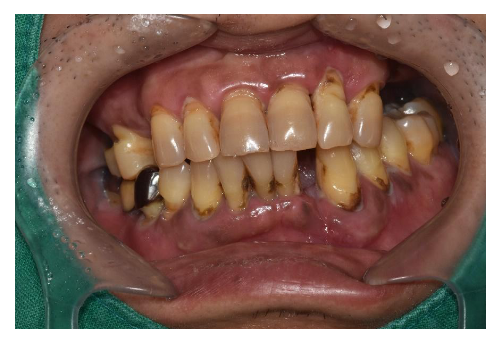

충치치료

1 치과공포증 치료 케이스

안녕하세요.대표원장 손승환 입니다.오랫만에 블로그 글로 인사드리는 것 같네요.요근래 환자분들이 많이 찾아주셔서 너무 정신없..